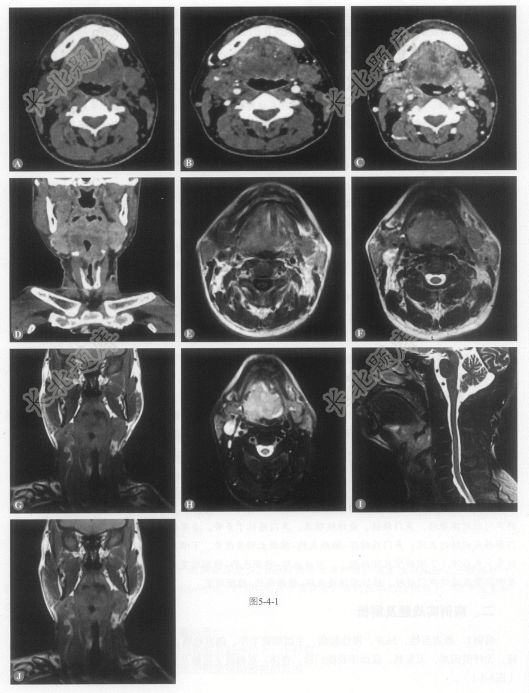

[材料题] 患者男性,56岁,慢性起病,主因咽痛半年,偶有呛咳,伴咽异物感,伴干咳,伴声音嘶哑,无呼吸困难,无发热,就诊于我院门诊。查体:双侧颌下可触及肿物,质硬,与周围组织界限不清(图5-4-1)。

多项选择题1.病变累及的范围:

多项选择题2.根据所给图像,淋巴结增大的区域为:

多项选择题3.根据以上临床资料与CT、MRI表现特点,该病例最可能的诊断为下列哪一项:

多项选择题4.病变的分期:

多项选择题5.该病变手术方式的选择: